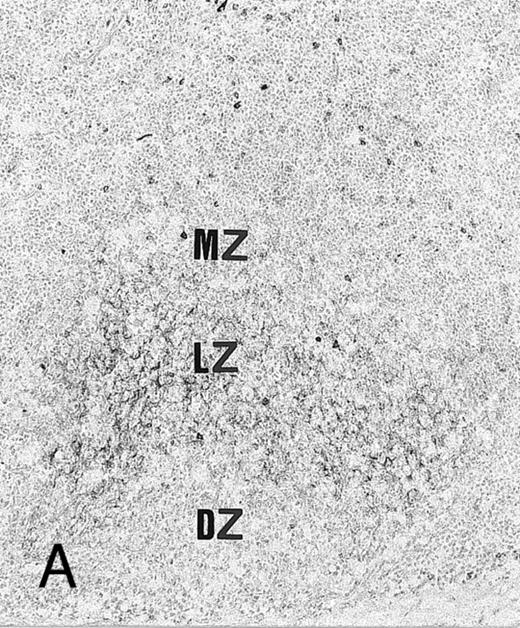

Expression of TGF-β and TGF-β receptor II in tonsillar lymphoid follicle. (A) Immunostain of TGF-β. There is the reticular and dotted positive stain in the apical and basal light zones but not the other follicular zones. MZ, mantle zone; LZ, light zone; DZ, dark zone. Counterstained with methyl green. Original magnification × 132. (B) Immunostain of TGF-βR II. There is the reticular expression in the apical light zone. OZ, outer zone; ALZ, apical light zone; BLZ, basal light zone; DZ, dark zone. Counterstained with methyl green. Original magnification × 100. (C) Immunocytochemical single staining (red color) of TGF-β on an isolated FDC. Original magnification × 1,280. (D) Double staining of TGF-β and R4/23 on the same FDC. There is a positive signal in the cytoplasm of FDC (brown). Counterstained with hematoxylin. Original magnification × 1,280. (E) In situ hybridization of TGF-β cDNA in the ALZ. Dendritic-shaped cells heavily labeled (arrows). Scattered lymphocytes are also stained (arrowheads). Uncounterstained. Original magnification × 860. (F) In situ hybridization of a TGF-βR II oligonucleotide in the ALZ. Many dendritic-shaped cells are strongly positive. Uncounterstained. Original magnification × 400.

Immunohistochemically, the ALZ but not the other follicular zones was positive in the reticular meshwork and dotted patterns for TGF-β and TGF-βR II (Tables 3 and 4 and Fig 1A and B). Immunocytochemically, FDCs isolated with MACS were single-positive for TGF-β in their cytoplasm (Fig 1C) and double-positive for TGF-β and R4/23 (Fig 1D). Less frequently, lymphocytes isolated with MACS were positive for TGF-β (<1%). In situ hybridization using a cDNA probe for TGF-β showed the reticular and dotted patterns only in the ALZ labeling cells such as dendritic-shaped cells and lymphocytes and the scattered pattern labeling vascular walls within the whole LF (Table 5 and Fig 1E). In situ hybridization using an oligonucleotide probe for TGF-βRII showed only the reticular pattern in the ALZ labeling dendritic-shaped cells (Fig 1F). Vascular walls within the whole LF were also reacted. Follicular lymphocytes were negative. RT-PCR of samples obtained from the whole tonsillar sample as well as the GC and EGC showed a single-positive band of TGF-β (161 bp; Table 6 and Fig 2A).